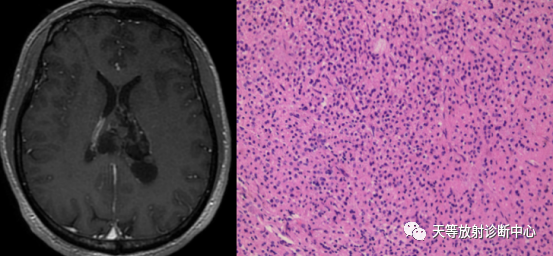

病例3:中枢神经细胞瘤

MRI显示肿瘤位于侧脑室,增强后肿瘤轻度强化,肿瘤组织由大小一致的小圆细胞构成,富含分枝状血 管,可见核周空晕(HE×200).(刘颖,姜晨霞,王燕,张青.中枢神经细胞瘤 13 例临床病理分析并文献复[J].临床与病理杂志,2020.40(8):1949-1952.)